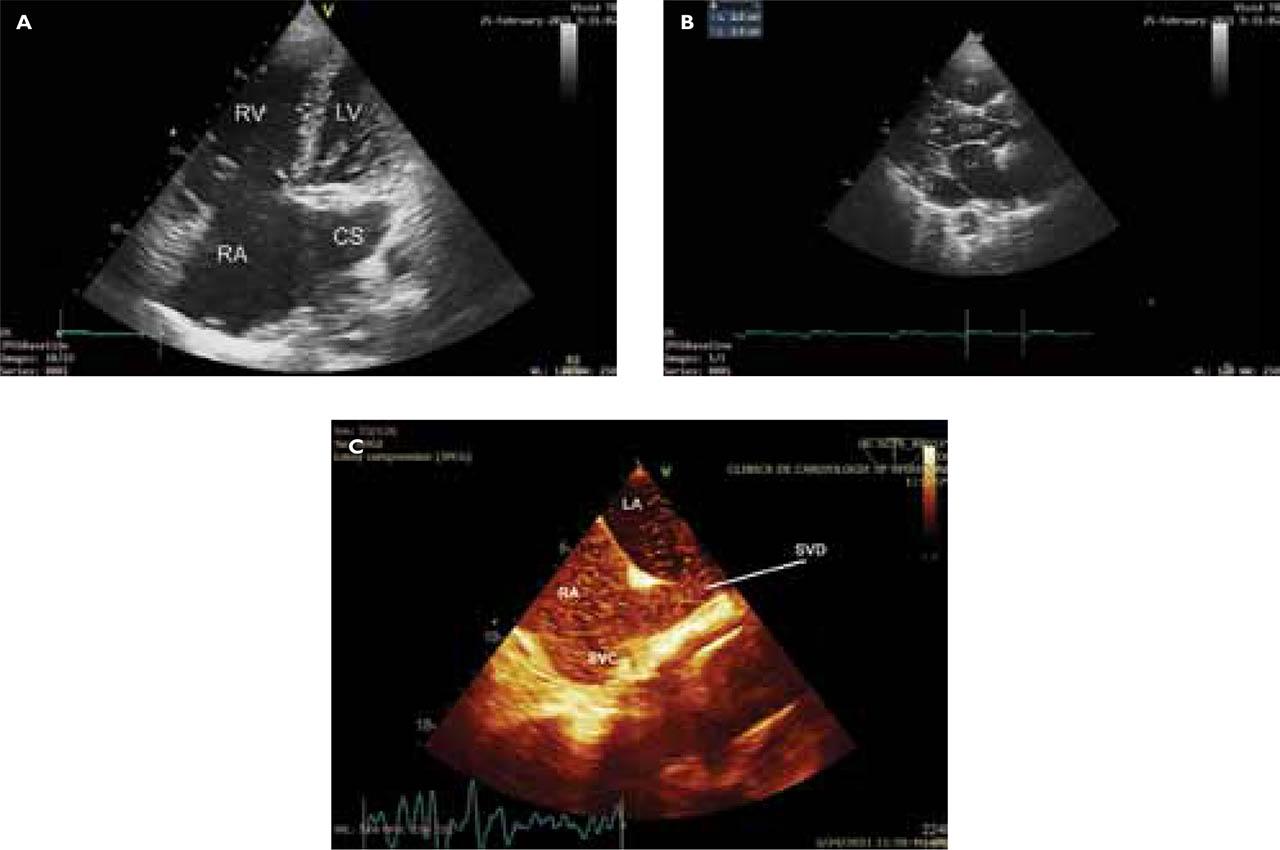

Figure 2

A. TTE: apical 4 chamber view with posterior tilt shows clearly dilated right heart chambers and CS. B. TTE: left parasternal long-axis view showing a dilated CS (diameter 24 mm), descending thoracic aorta (DA) of 20 mm. C. TOE longitudinal plane (bicaval view) showing a superior SVD with right-to-left shunt evident as contrast study with agitated saline solution moves through the SVD to LA; SVC, superior vena cava; RA, right atrium; LA, left atrium. D. TOE view of sinus venosus ASD: enlarged RA, and color flow showing bi-directional shunt.